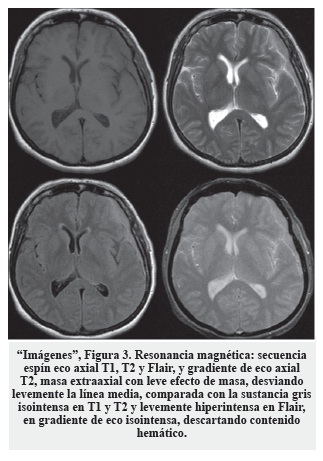

El examen físico reveló dolor focal en la región cervical y edema en el miembro superior izquierdo. Los estudios de imágenes (tomografía y resonancia cerebral) mostraron una lesión en la pared lateral del seno cavernoso con extensión a la fosa posterior y tentorio, siguiendo las meninges hasta el agujero magno. Como probable diagnóstico se consideró meningioma de comportamiento agresivo ("Imágenes", Figura 1).

En conjunto, los servicios tratantes de neurología oncológica y hematología decidieron realizar el protocolo de quimioterapia basado en metotrexate con altas dosis, logrando una reducción próxima al 80% en el volumen de la lesión ("Imágenes", Figura 1).